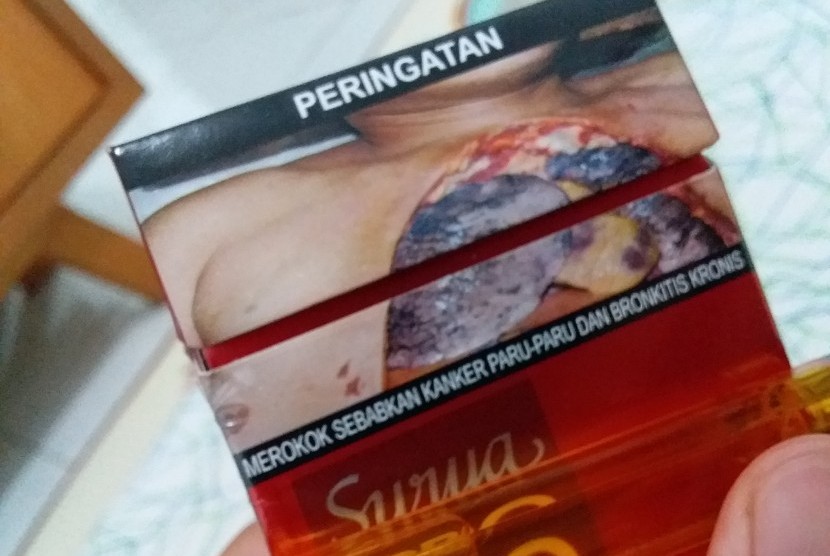

Bahaya Merokok Seminar Tb Di Puskesmas Pdf

Bahaya Merokok Seminar Tb Di Puskesmas Pdf